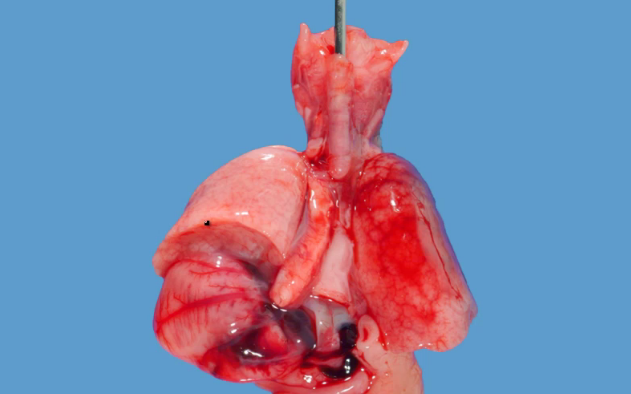

What are the 4 common clinical presentations in patients with the condition shown below?

This is a tracheo-esophageal fistula. This will present with 1) vomiting from food getting stuck in the proximal atretic esophagus, 2) polyhydramnios from the fetus not being able to recycle amniotic fluid, 3) aspiration from gastric acid coming up the distal esophagus into trachea and 4) abdominal distention from tracheal air flowing into the distal esophagus and on to the stomach.